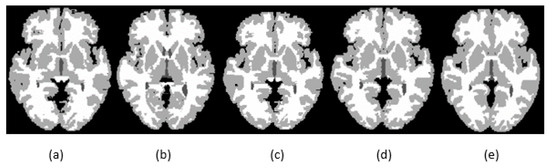

4.1. Segmentation Experiments